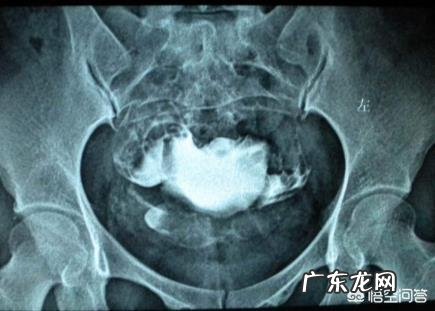

输卵管堵塞多数都是因为后天的炎症(盆腔炎、附件炎、阴道炎)关系造成的,这些炎症问题受到会导致输卵管的粘膜发生炎性改变,使得输卵管上皮出现退行性或成片脱落,以致于输卵管粘膜出现粘连,继而管腔部位粘连或者是伞端闭锁 。

盆腔炎导致的输卵管堵塞:有盆腔手术史的粉丝,其中3/4会出现输卵管粘连的情况 。盆腔炎现在一般分为急性和慢性的两种 。对于急性的盆腔炎可以导致→弥漫性腹膜炎、败血症、感染性休克,不及时治疗转变为慢性可以引发→输卵管堵塞不孕、输卵管通而不畅时宫外孕,严重影响到粉丝的健康、婚姻甚至是生活 。

粉丝如果存在盆腔炎问题,主要该方面疾病的及时治疗,严重的盆腔炎问题会导致子宫与直肠之间出现脓肿,即便这些炎症消退以后,卵巢和输卵管的粘连也很难避免,导致输卵管伞端粘连闭锁,卵巢表面的包膜增厚硬化,卵子无法排出 。